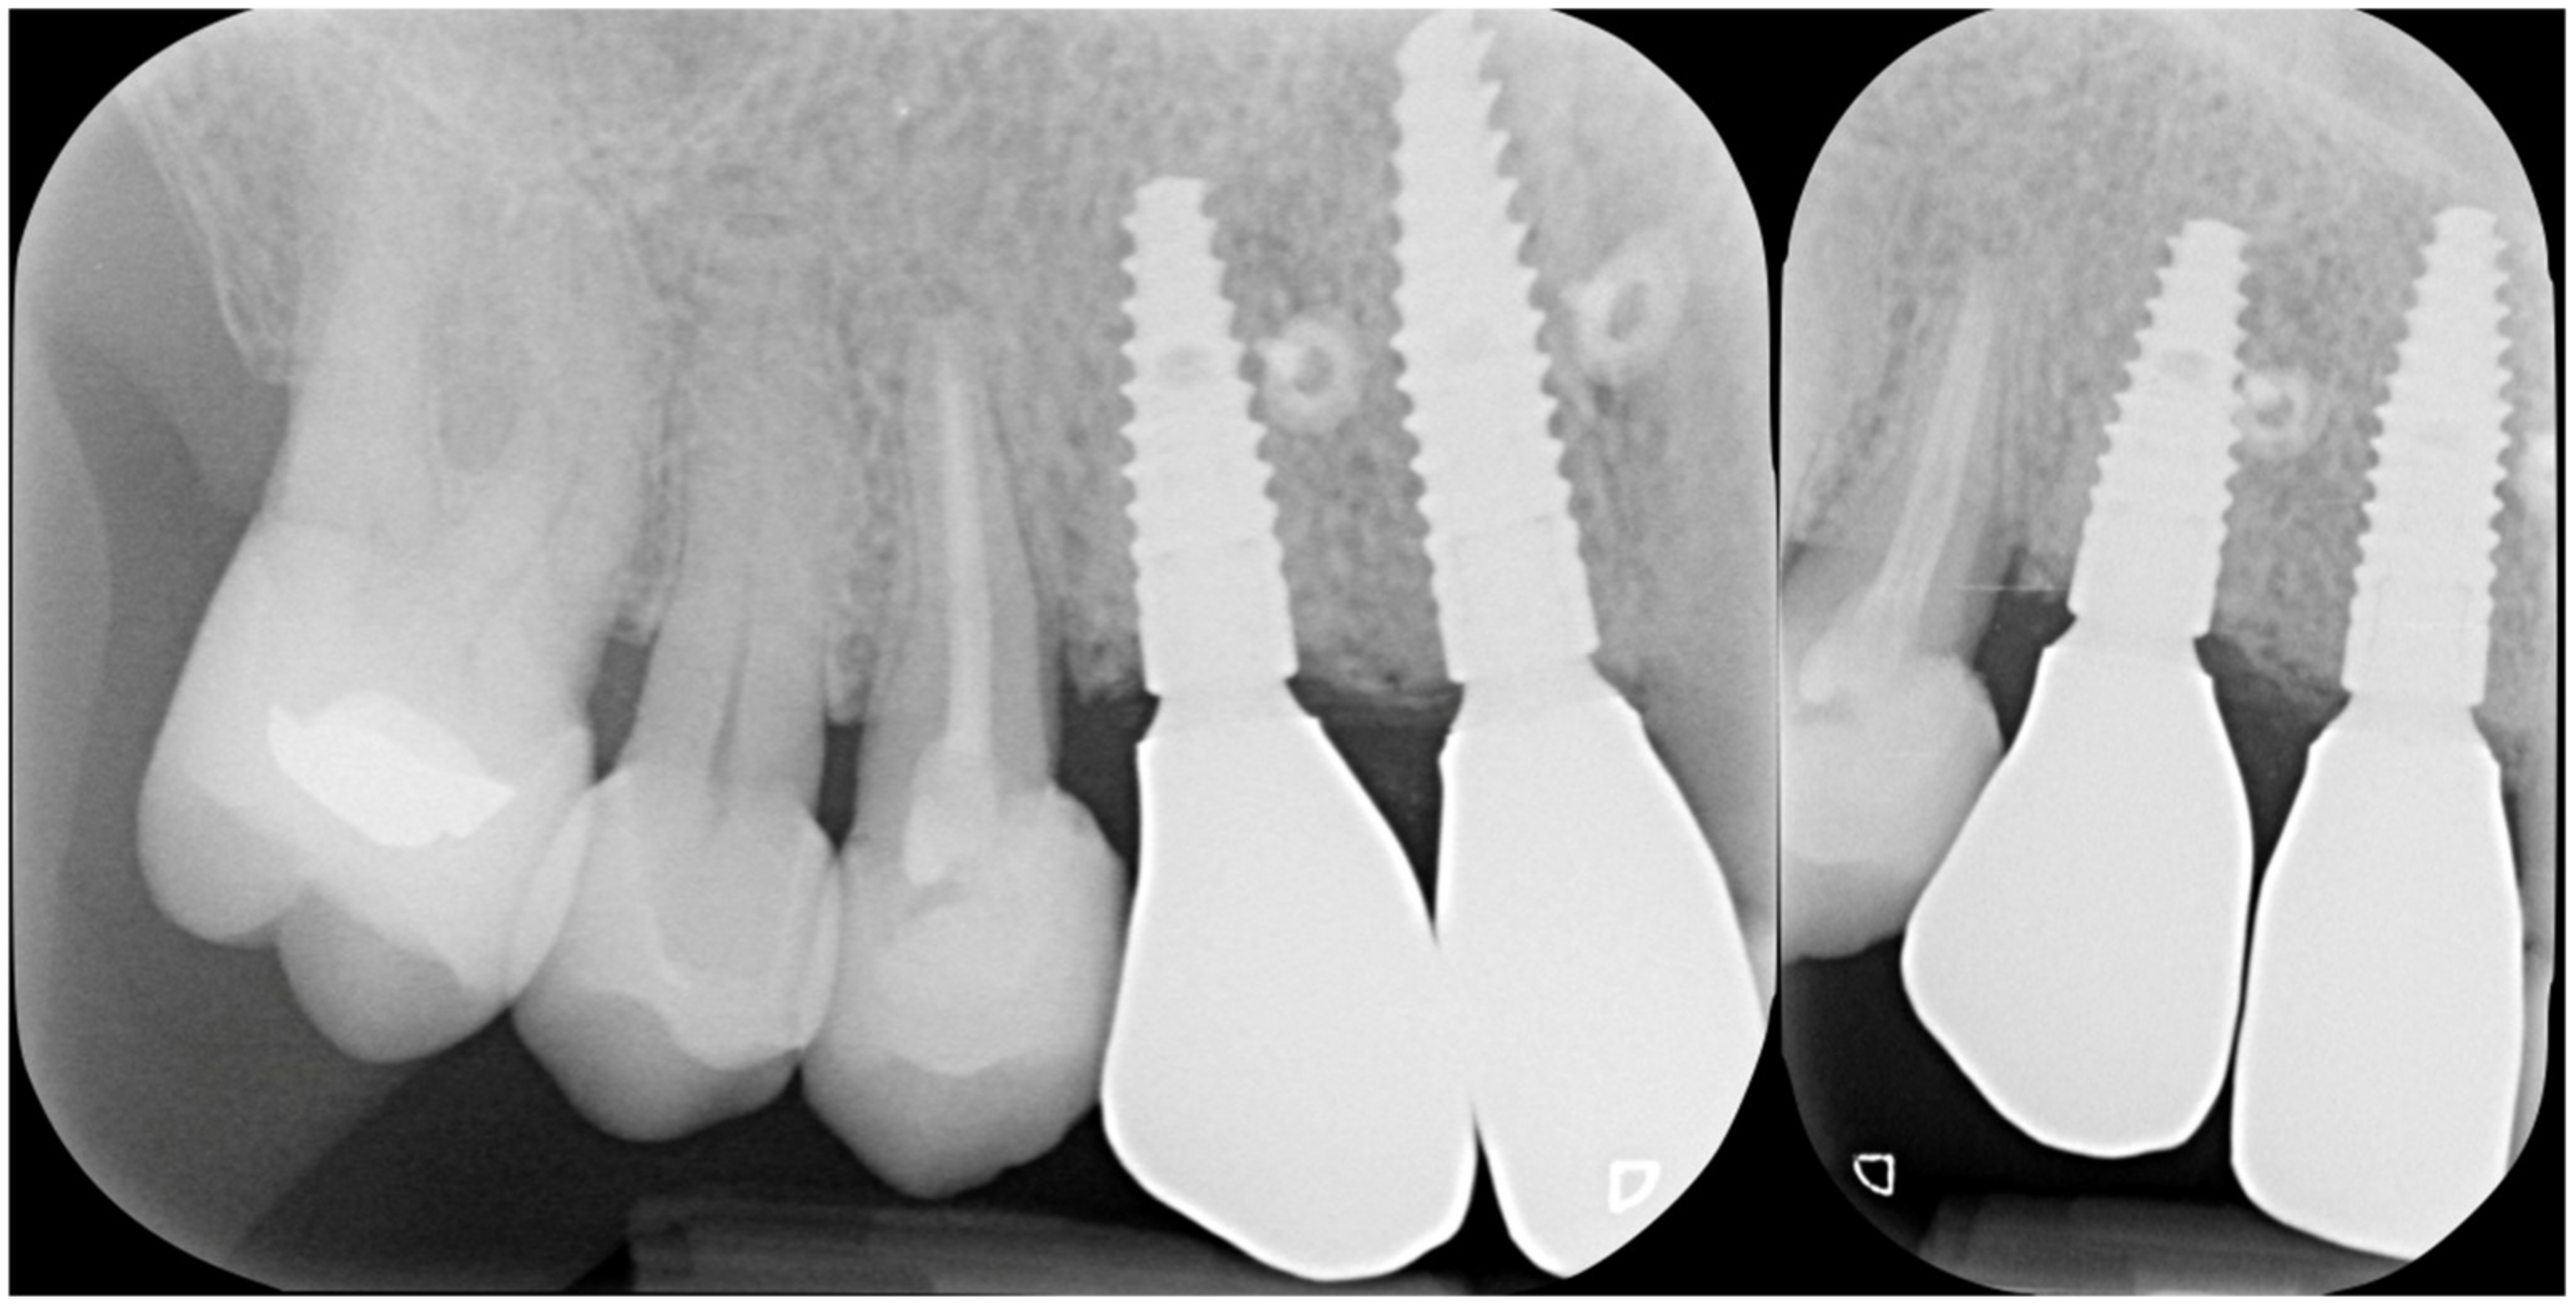

The radiographs at baseline and after completion of the prosthetic restoration also show the GTR effect of GBR in this case on the natural teeth, aside from the expected effect on bone and implants. Both bony peaks to the distal of 11 and mesial of 14 are coronal to the head of the fixture and support interdental papilla (Figure 20 and Figure 21). It is possible to appreciate in the radiographs the stability and good mineralization of the grafted area.

Figure 20.

The supra-crestal component of the bone lamina (blue) and the GTR effect near tooth 11 (white arrow).

Figure 21.

Rx of follow-up completion of restoration (left) and at 3 years after load (right).